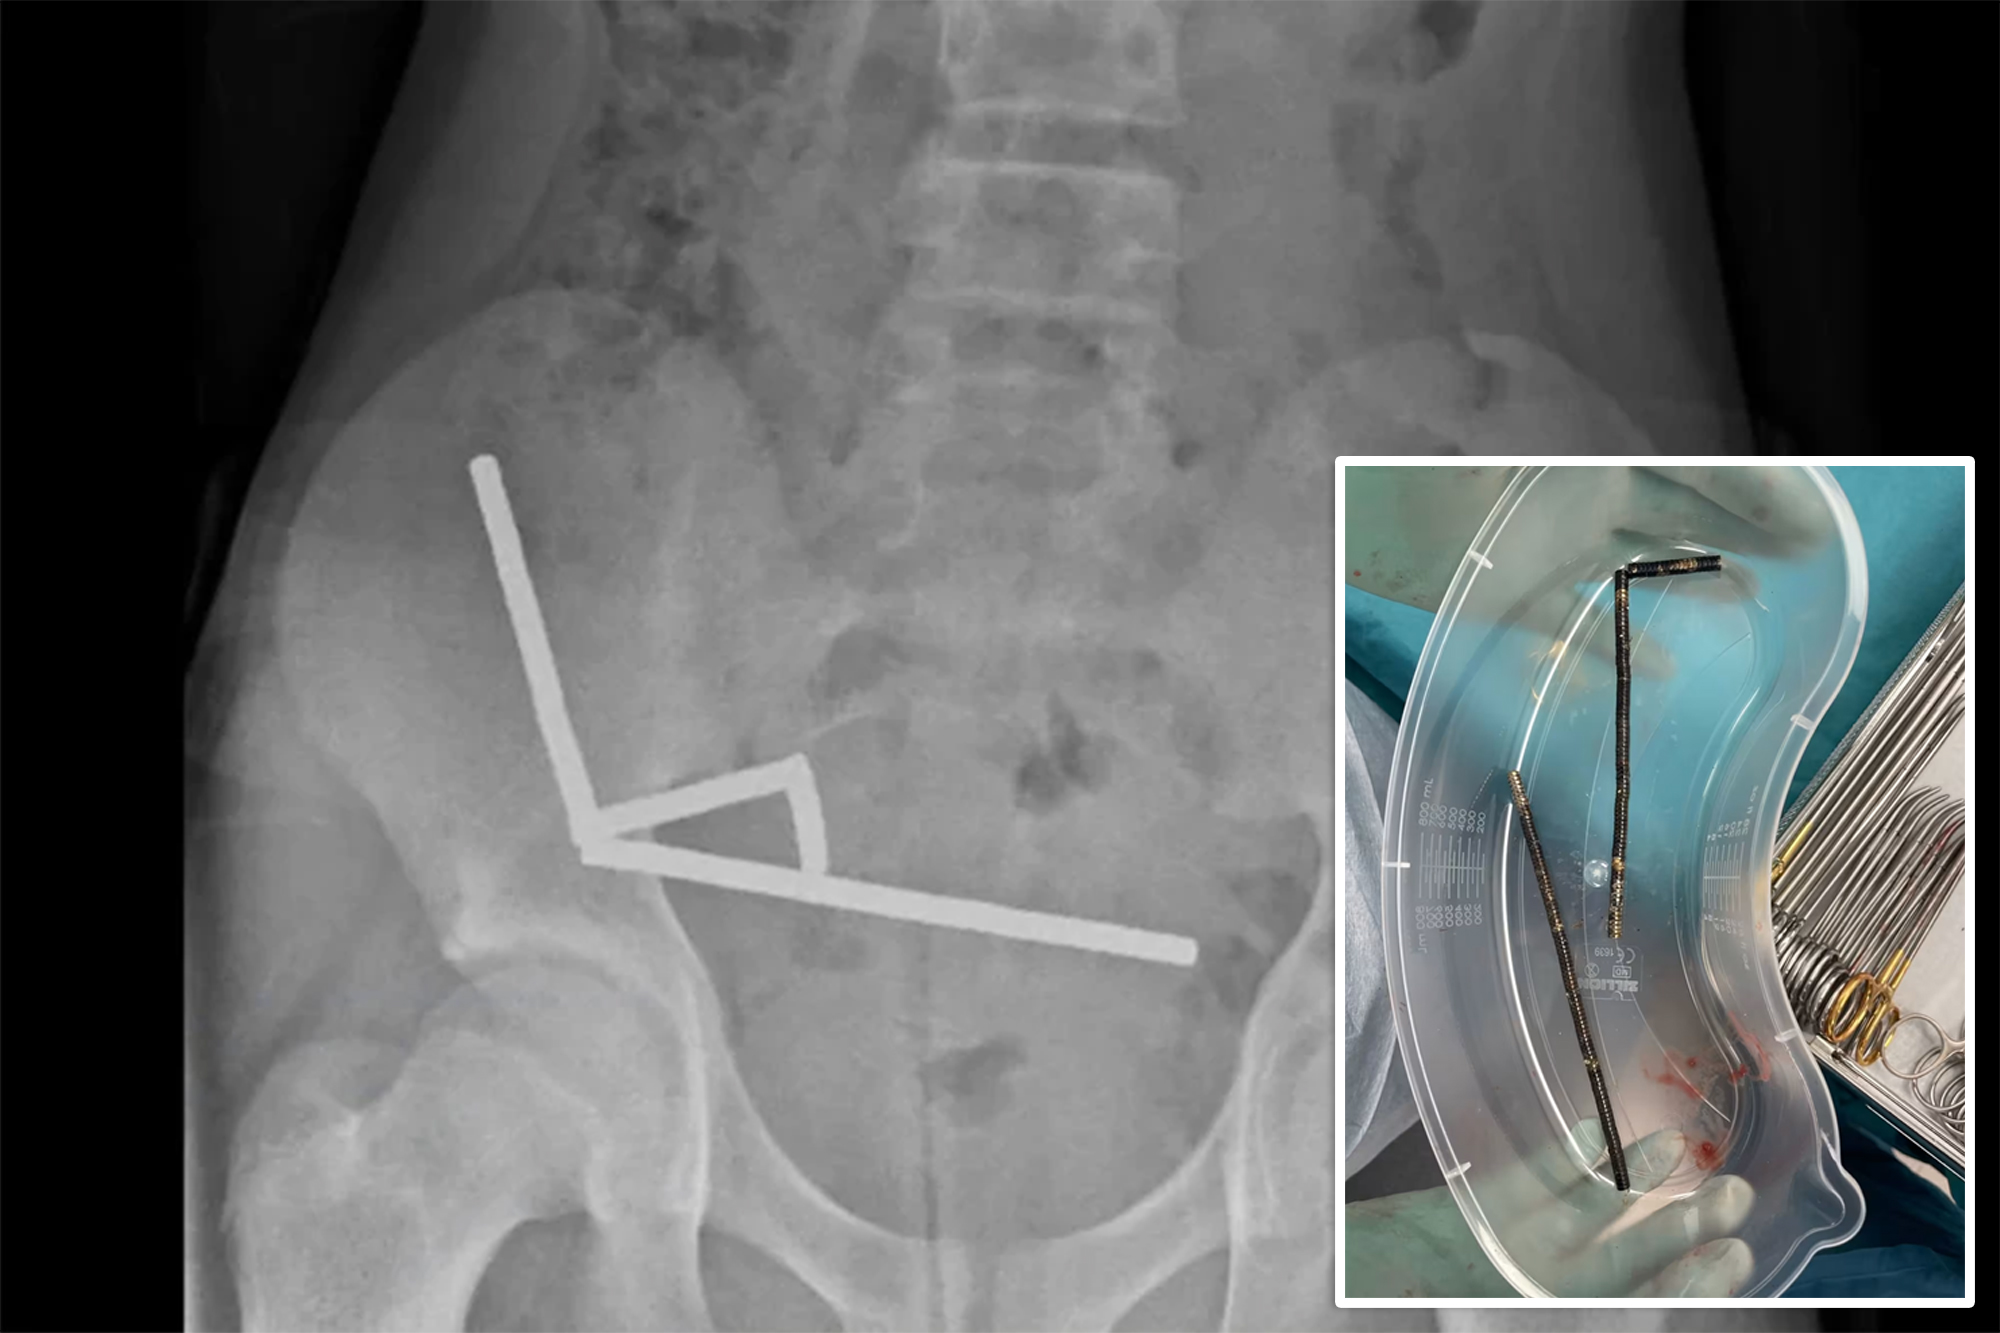

Upon examination, X-rays revealed multiple chains of magnets lodged in different sections of the boy’s intestines. The magnets had clumped together, restricting blood flow to surrounding tissue and causing areas of necrosis, or dead intestinal lining. Surgeons performed an urgent operation to remove both the magnets and the damaged sections of the bowel. After the eight-day hospital stay, the boy was discharged, as detailed in a case report published in the New Zealand Medical Journal.

The magnets involved in this case measured 5 by 2 millimeters. The surgical team reported that they had formed into four linear clusters within the boy’s intestines, creating a dangerous situation by pinching the tissue between them. Physicians have noted that patients who undergo similar magnet removal surgeries frequently encounter long-term complications, including bowel obstructions, hernias, and chronic abdominal pain.